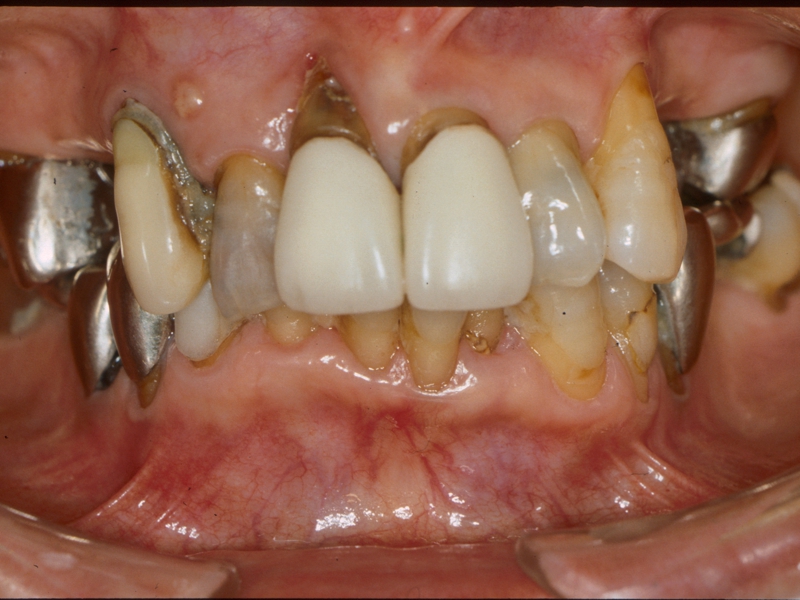

初診時

歯周治療、部分矯正治療、インプラント治療終了後5年